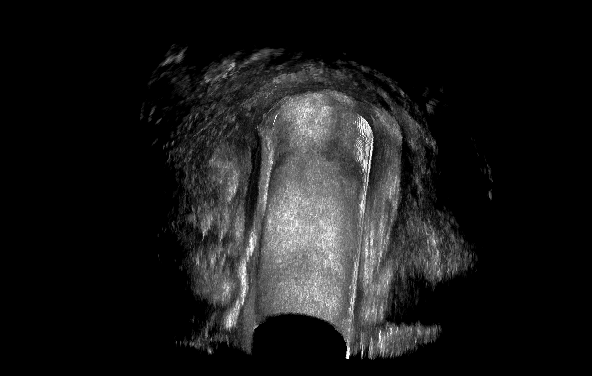

直肠腔内超声是判断肛瘘情况的最重要的辅助手段之一。直肠腔内超声可以清楚显示一般瘘道的形态和走行轨迹、内口的位置、是否存在次级分支、是否合并慢性脓腔及其深度与范围等,可以对大多数肛瘘做出准确的诊断。但对于瘘道路径不清晰,内口不能准确判断以及反复手术造成图像不易识别的病例,常规诊断方法就显示出它的不足。

针对上述情况,肛瘘过氧化氢超声造影诊断技术(HPUS)应需而生,它是经由肛瘘外口处注入过氧化氢溶液,这样可以显著增强瘘管的回声效果,使之由低回声变为强回声,从而达到明确诊断的目的。

瘘道与周围组织回声存在明显的差异,大多数情况下瘘道主支、分支的识别是比较容易的,但在反复发作或术后复发的病例中可能存在辨别困难,其主要原因是瘢痕与瘘道相近的低回声造成了鉴别困难。其次,瘢痕后方宽大的声影影响了其深方组织的扫查。过氧化氢超声诊断技术应用后,经肛瘘外口注入的过氧化氢迅速形成无数微气泡,瘘道内出现强回声气体线条,与周围组织回声形成鲜明对比,瘘道路径被勾勒出来,可以增强瘘道的显示程度,检查出常规腔内超声可能遗漏的病变,为临床制定手术方案提供准确的影像依据,彻底清除感染,避免术后复发。